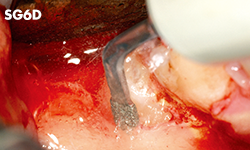

Unilateral anterior mandibular sampling

Excision of bone torus

Anterior mandibylar harvesting

Mandibular harvesting at approach stage

The cutting part is bone torus